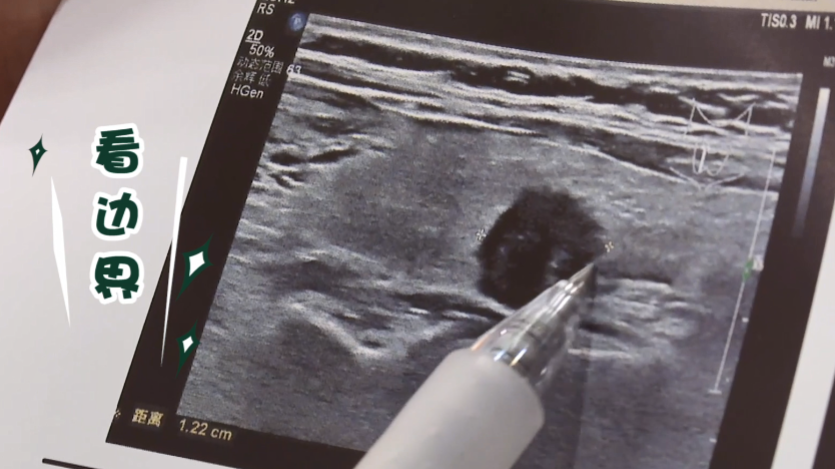

甲状腺又称“生命腺”, 对人体健康至关重要。 甲状腺结节是什么? 甲状腺结节是通过影像学检查观察到的甲状腺细胞增生后出现的团块,包含良性甲状腺结节和恶性甲状腺结节。 良性甲状腺结节多由甲亢、甲减、甲状腺炎等问题引起,一般包含增生、非肿瘤性结节、良性肿瘤等。 恶性甲状结节中最常见的就是甲状腺癌。 脖子上莫名出现的“小疙瘩” 它是不是癌症? 是不是应该立即切除? 应该如何正确对待? 成为人们关注的焦点 面对甲状腺结节,不忽视不恐慌 天津医科大学肿瘤医院郑向前教授教您6招看懂甲状腺超声报告。 01 看分级 4级及以上的结节需要尽快前往正规医院就诊。 一般在常规的医院诊断结果中会给予一个定性的诊断。如果是4级或者4级以上,恶性肿瘤的可能性会比较大。 02 看边界 甲状腺恶性肿瘤的边界一般不是特别清楚,周边有毛刺样的改变; 而良性肿瘤的边界比较清晰,而且周边会有一个晕环。 03 看回声 回声通俗地讲是指肿瘤在超声中的深浅程度。恶性肿瘤一般是低回声或极低回声,低回声和极低回声在超声图中表现为一个深暗色的图形。 04 看钙化 微小钙化有可能是恶性肿瘤的表现。超声图中有一些小的亮点,提示肿瘤有微小的钙化,有恶性肿瘤的可能性。 05 看形态 恶性肿瘤的纵横比往往会大于1,也就是说它的长径和短径的之比会大于1,不是一个规则的圆形,可能是长条形的。 06 看血流 恶性结节往往会出现丰富而杂乱的血流。在超声图中可以看到黄色、红色和蓝色的斑点,这代表了静脉和动脉的一些血流的情况。恶性肿瘤一般血流比较丰富,而且杂乱。